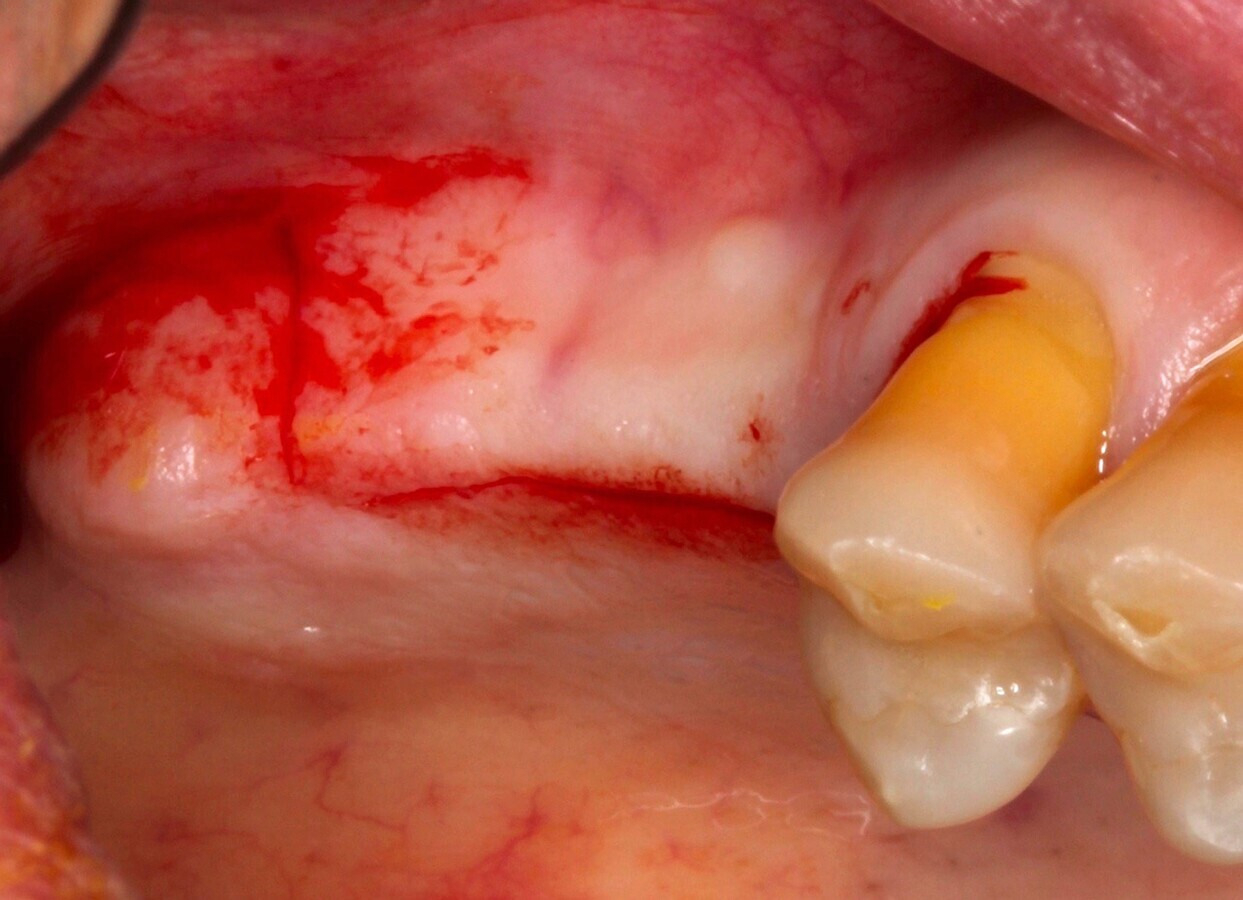

Fig. 1

Figura 1

1. Anestesia infiltrativa vestibular y lingual o palatina en la zona a intervenir.

2. Incisión paracrestal 2 mm hacia el palatino con hoja de bisturí 15C e intrasurcular al diente adyacente. Realización de la descarga de la distadora para una correcta visión del campo quirúrgico.